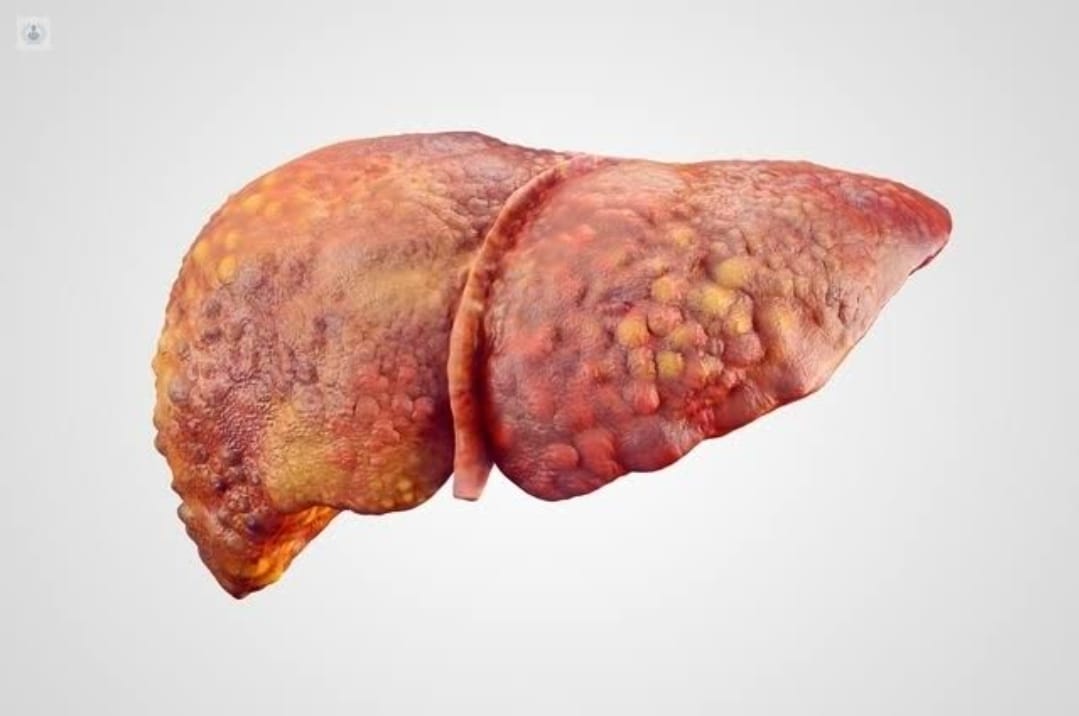

• Se considera que es graso cuando en células hepáticas están conformadas por más de 5% de grasa.

Se le conoce como hígado graso cuando se acumula mucha grasa en las células hepáticas y, aunque es normal tener un poco de grasa en estas células, se considera que es graso cuando está conformado por más de 5% de grasa.

En el hígado graso no alcohólico existen dos tipos: el Hígado graso simple en el cual hay grasa en el hígado pero, no existe inflamación o daño. Y está la esteatosis hepática no alcohólica, en la cual ya se presenta una inflamación y daños en las células del hígado y grasa. Sin tratamiento puede llegar a causar cirrosis o cáncer de hígado.

La especialista mencionó que la esteatosis hepática alcohólica, también conocida como hígado graso por alcohol, como su nombre lo indica, se presenta debido a un consumo excesivo de esta sustancia esta es la etapa más temprana de afección, si no se diagnostica a tiempo se puede volver una hepatitis alcohólica o cirrosis.